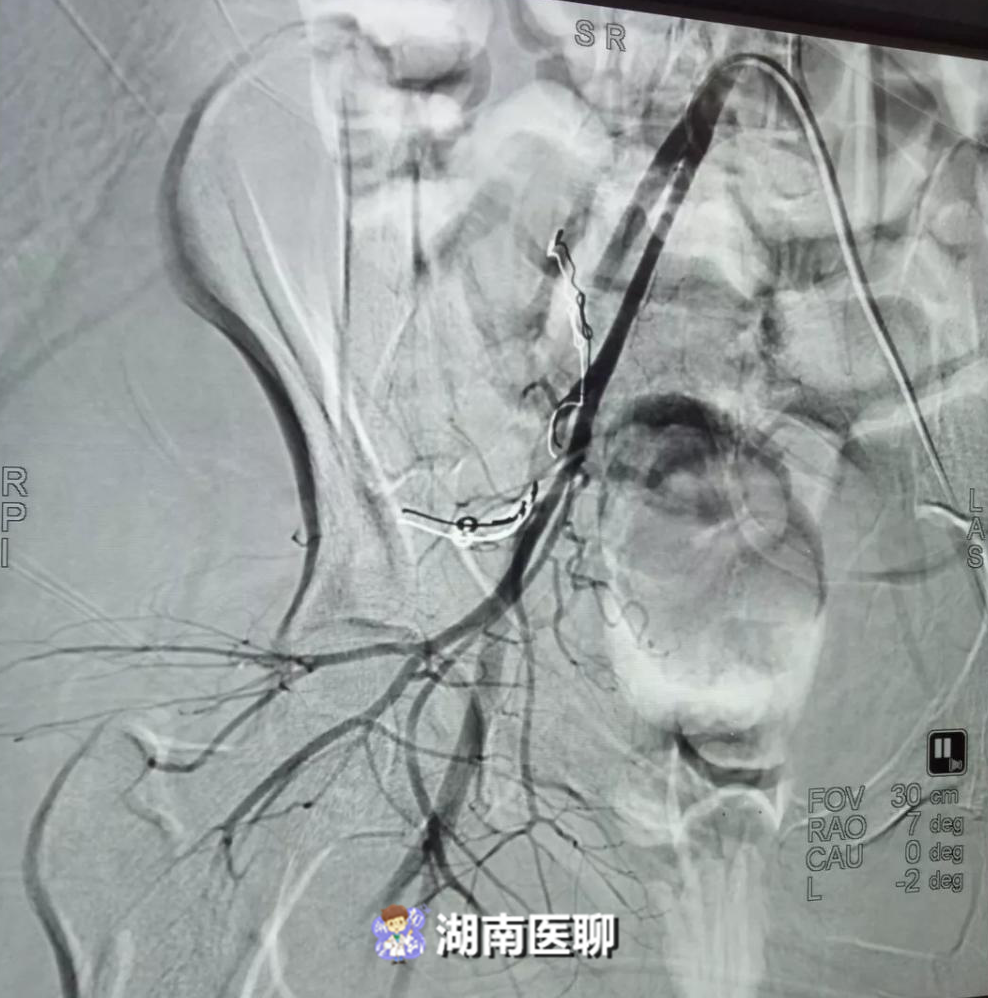

当天下午,医院介入科以李孝生博士为首的介入微创诊疗团队就为患者实行了介入造影栓塞止血。

共在其骨盆内找到四处出血点,通过输血及介入栓塞,患者的大出血终于止住了,血细胞逐渐得到纠正。